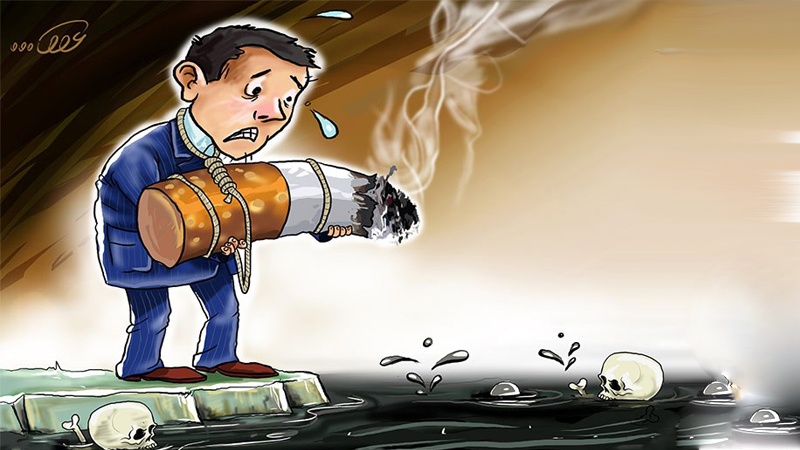

جگەرە ساڵانە ٦ ملیۆن کەس دەکوژێت

ڕاپۆرتێکی نوێ نیشانی دا کێشانی جگەرە نێزیک ٦ ملیۆن کەس دەکوژێت لە ساڵدا و تێچووە جیهانیەکانیشی زیاتر لە یەک هەزار ملیار دۆلار لە ساڵدا لە بواری تێچووی پاراستنی تەندروستی دەبێت.

بە پێی ڕاپۆرتی ڕێکخراوی تەندروستی جیهانی و ڕێکخراوی شێرپەنجەی ویلایەتە یەکگرتووەکان، بە بەرز بوونەوەی نرخ و ماڵیاتی دوخانیات دەتوانرێت ملیارەها دۆلار و گیانی ملیۆنان کەس بپارێزرێت.

نووسەرانی ئەو خوێندنەوە وتیان: سیاسەتەکانی کۆنترۆڵی دووکەڵەکان، جودا لە هێنانە خوارەوەی نەخۆشینەکانی دڵ و شێرپەنجە، دەتوانێت ڕێژەیەک پارە بۆ وڵاتەکان سروست بکات تا بۆ تەندروستی و گەشەی ئابووری کەڵکی لێ وەربگیردرێت.

دوکتۆر ئولنگ چستنۆ جێگری بەرپرسی نەخۆشیە نامافەتەکان و تەندروستی دەروون دەڵێت: ئەو ڕاپۆرتە نیشانی دەدات کە کاریگەری ئابووری توتون و تەنباکوو لە سەر وڵاتەکان و تەواوی خەڵک، زۆر زیادە. پیشەی دووکەڵەکەن، بەرهەمێک دەنێرنە بازاڕەوە کە بە ملیۆنان کەس بە شێوەی پێش وەخت دەکوژێت، ڕێژەیەکی پارە دەدزێت کە دەتوانرێت بۆ مادەی خۆراکی و پەروەردە و تێچووە دەرمانیەکانی ڕێژەیەکی بەرچاوی خەڵک خەرج بکرێت.

توتون و تەنباکۆ یەکێک لە هۆکارەکانی نەخۆشیە نامافەتەکان لەوانە نەخۆشینەکانی دڵ، شەکرە و نەخۆشینەکانی پوفن. دابەزینی بەکارهێنانی دووکەڵەکان بەشێکی بەرچاو لە تێکۆشانەکان بۆ دابەزینی یەک لە سەر سێی مەرگی پێش وەختی بەجێماو لە نەخۆشینە نامافەتەکان تا ساڵی ٢٠٣٠ ە.